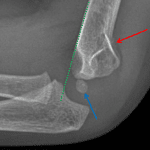

- Acute mildly displaced supracondylar fracture with posterior angulation

- Elbow joint effusion

Acute mildly displaced supracondylar fracture with posterior angulation.

Elbow joint effusion.

Radiocapitellar alignment is maintained.

- Look for anterior offset of the anterior humeral line (should intersect the middle third of the capitellum, but in the case of supracondylar fracture will intersect the anterior aspect or may miss the capitellum entirely), which may be the only sign of a fracture